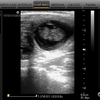

Diagnostico Reproductivo y Sanitario, ecografía reproductiva, IATF, colecta, evaluación y congelación de semen bovino, cirugía general y ginecológica.

Cordial saludo Dr. Alfredo! Soy Medico Veterinario, me interese mucho en su respuesta ya que trabajo en el area de Lecheria especializada. Tengo un caso especial en este momento: una finca con aproximadamente 50 vacas, promedio de produccion diaria 20 litros, alimentacion con balanceados 3 kg animal dia como suplemento y pastoreo con grámineas, predominio raza Holstein, con 4 animales con muerte ...